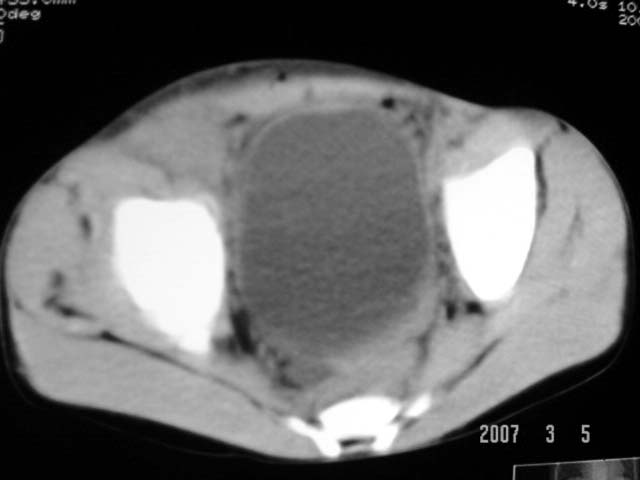

以下是引用dyqct在2007-3-5 10:28:00的发言:[br]右髂窝肿块。[br][br][br][br]